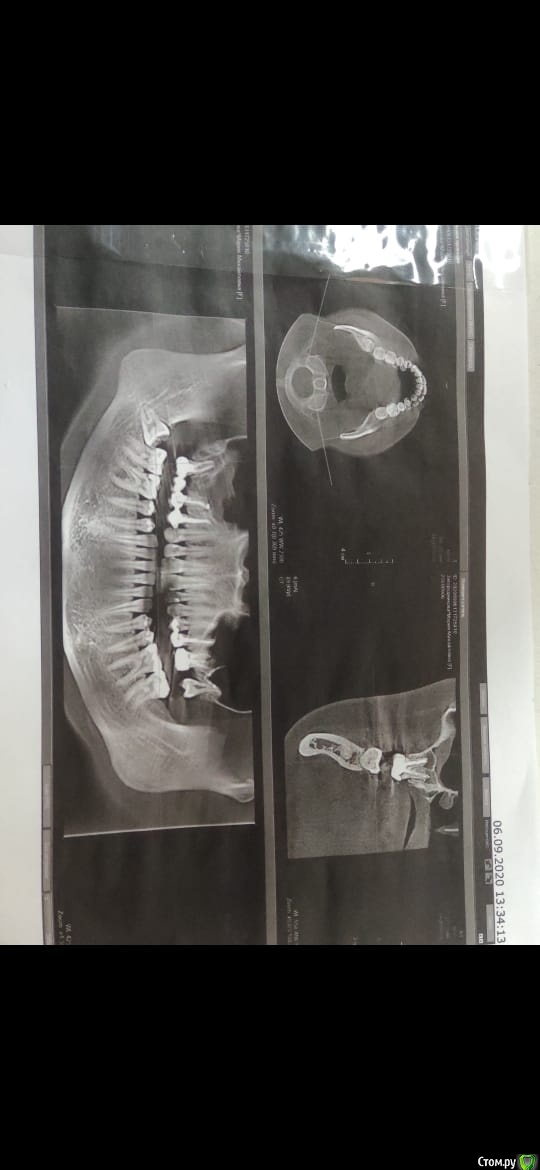

Добрый день! Обращаюсь к Вам за помощью, так как мнения врачей разделились, а я уже и не знаю, что думать. Над 5-м зубом возник свищ, сейчас он есть уже на протяжении 3-х месяцев, началось с того, что летом был гайморит и было сильное давление на область зубов (там, где установлен мост), в итоге, пила антибиотики и в целом состояние улучшилось. При этом не проходило ощущение давления в пазухе, стоматолог предложила проставить в десну линкомицин, дабы воспаление уменьшилось, после проставленных уколов, образовался свищ, тяжесть в пазухе так же присутствует. Стоматолог-терапевт говорит подождать, может, пройдет. Хирург говорит удалять 5 и 7, ставить имплантаты. Прилагаю снимок и прошу вашей помощи. Что же делать в данной ситуации? Есть ли шанс на то, что зуб можно сохранить? Может, стоит сделать резекцию верхушки?

Один снимок до мостовидного протеза (2019 год), второй сентябрь 2020.

Зуб 17, по моему мнению, придётся удалить; про 15 недостаточно информации. Неплохо бы свежую комп. томографию посмотреть (хотя бы от 09.2020), а не снимки скришотов с монитора. Постарайтесь выложить. Инструкция, как это сделать в самом начале пациентского раздела.